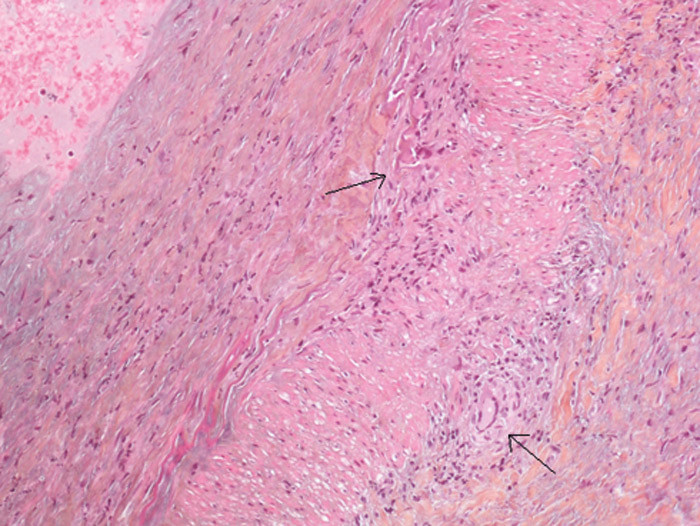

Pasienten ble innlagt i Nevrologisk avdeling med mistanke om sentralarterieokklusjon eller temporalisarteritt. Nevrologisk undersøkelse var upåfallende, med unntak av visustap venstre side. Pasienten hadde ikke hodepine. Temporalisarterien var verken hoven eller trykkøm, CRP var 19 mg/l (referanseverdi < 5 mg/l) og senkningsreaksjonen var 25 mm/t (referanseverdi < 30 mm/t). Ultralydundersøkelse av temporalarterien viste hypoekkoisk halo i arterieveggen som tegn på veggødem (bildet til høyre). Biopsi viste kjempeceller samt inflammatoriske forandringer i og rundt arterieveggen (bilde kun i Tidsskriftets nettutgave) og bekreftet diagnosen temporalisarteritt.